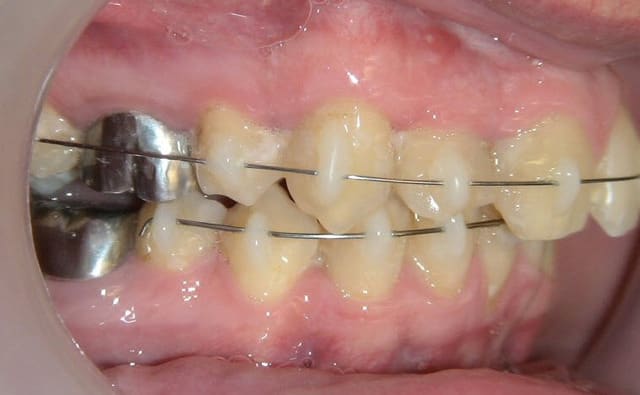

Ca y est ... mes 3 premiers cas de Dancha en pré implantaire.

Je sais je vais me faire lapider et critiquer mais c'est bien pour ca que je vous montre ces 3 cas.

contrôle à 1 mois du cas numero 2. Tout marche comme prévu. Encore mille mercis Daniel. Ta technique a beaucoup plus à mes confrères suédois !

Cas nr 2 controle  1mois kps86j - Eugenol